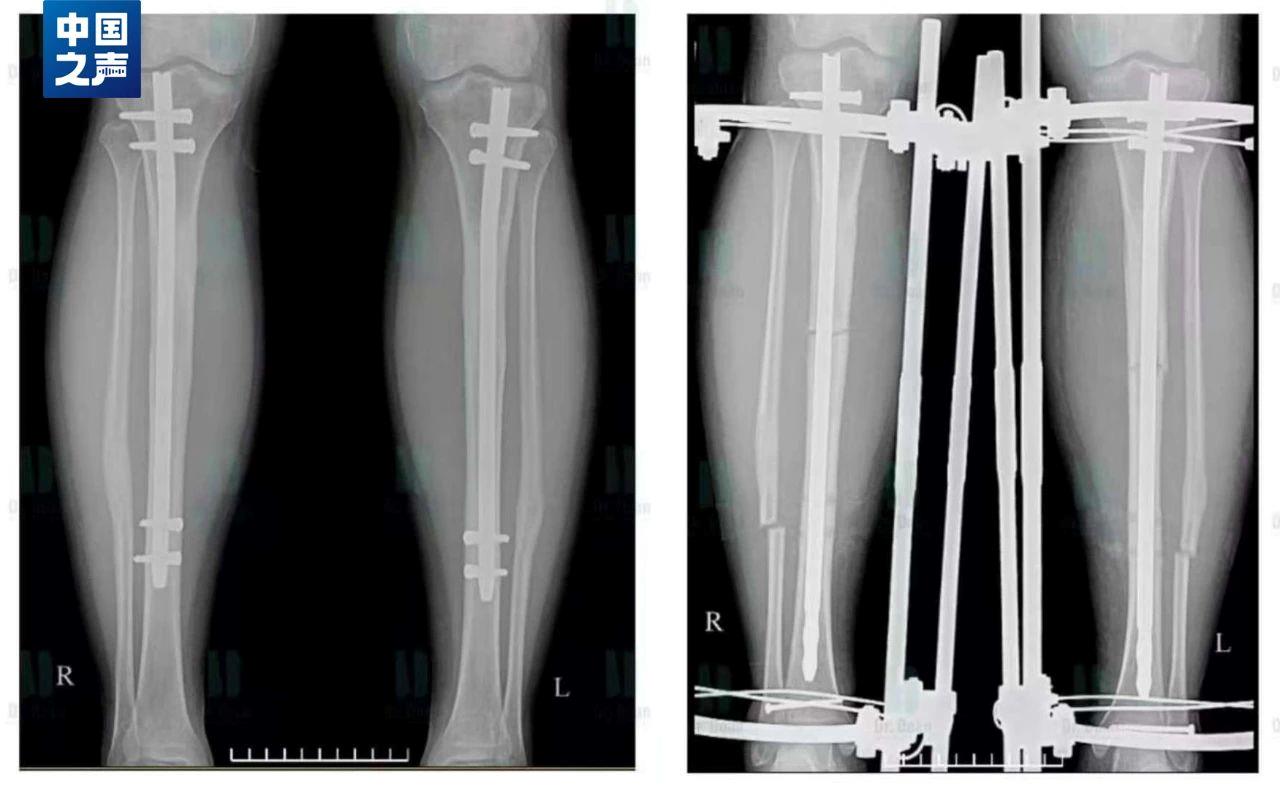

“断骨增高术”的原理是使用骨科截骨术,在小腿或大腿把已经闭合的骨生长线重新“打开”,并在体外安装一种具有牵伸作用的肢体延长器,根据每个人的组织再生能力和特点,每天以0.5毫米到1毫米的速度将肢体缓慢延长。而延长的方法就是使用工具旋转肢体延长器,起到牵引拉长的作用。我国严令禁止健康人进行这一危险手术。

实施“断骨增高术”后拍摄的X光片,钢钉直接钉进腿骨当中,腿周围还增加了一圈固定设备起牵引作用。